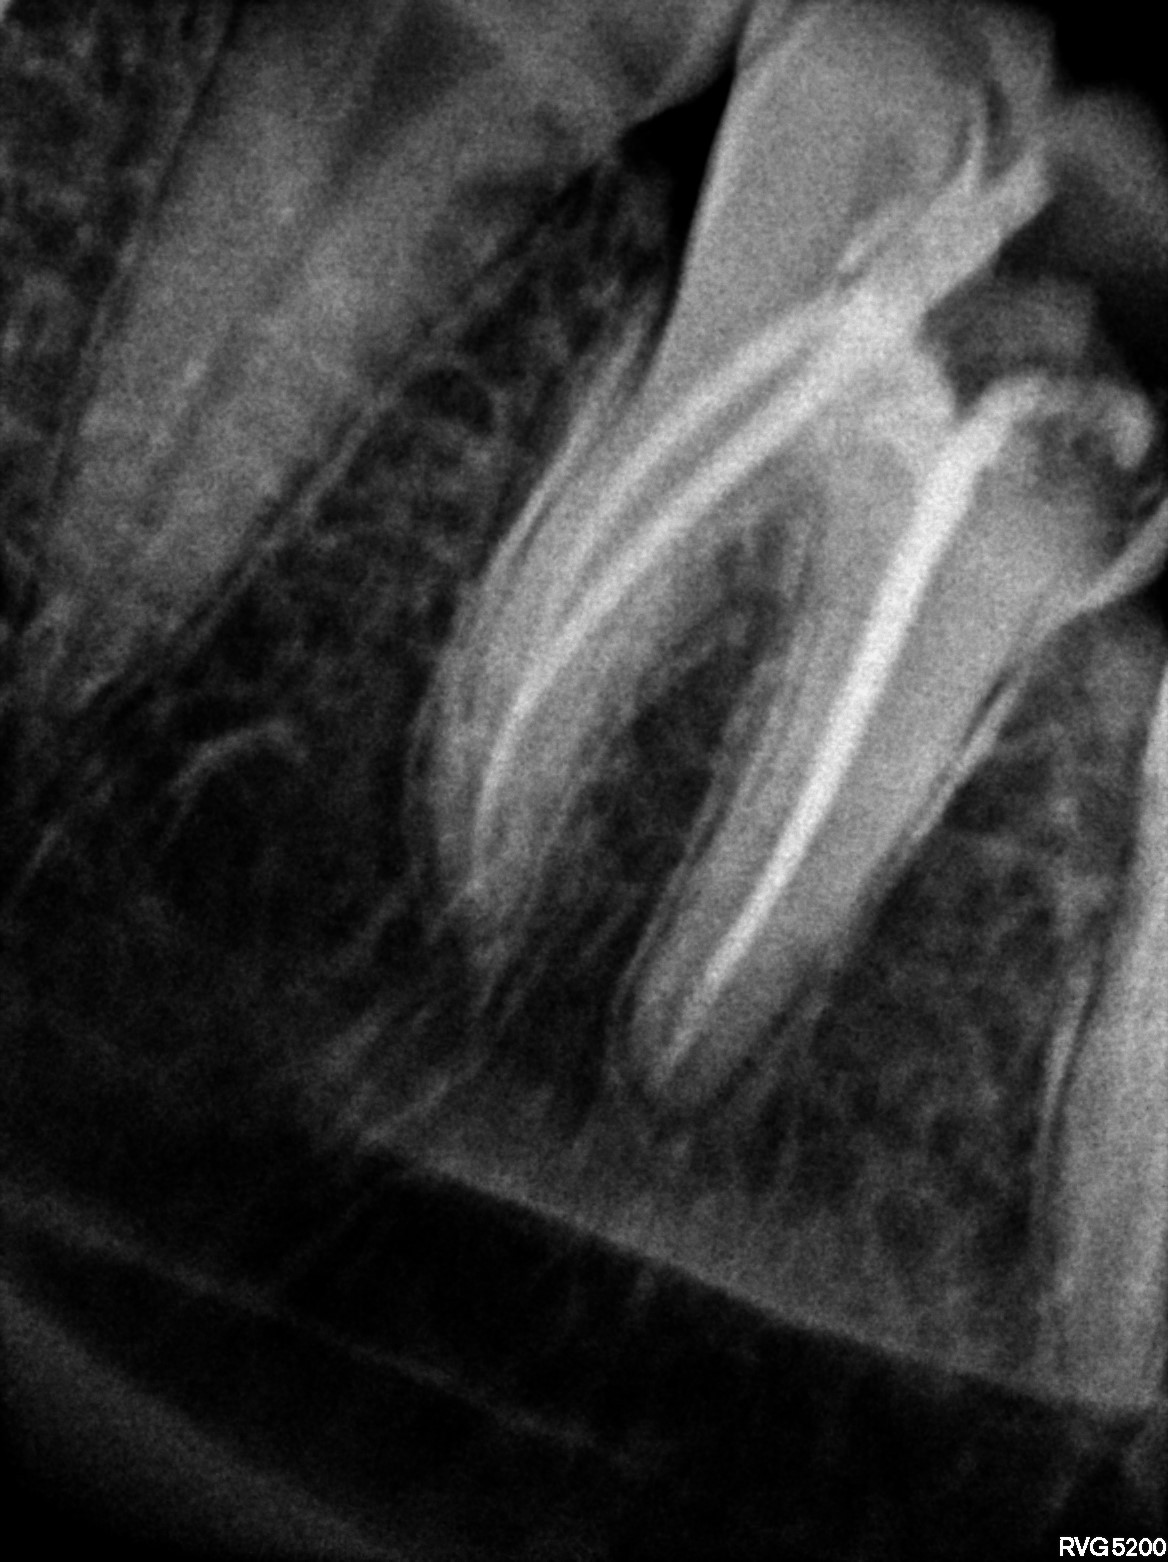

Dental Radiographs FHIR: DocumentReference · LOINC 24641-7

xray_1772613109_4.jpg

24641-7